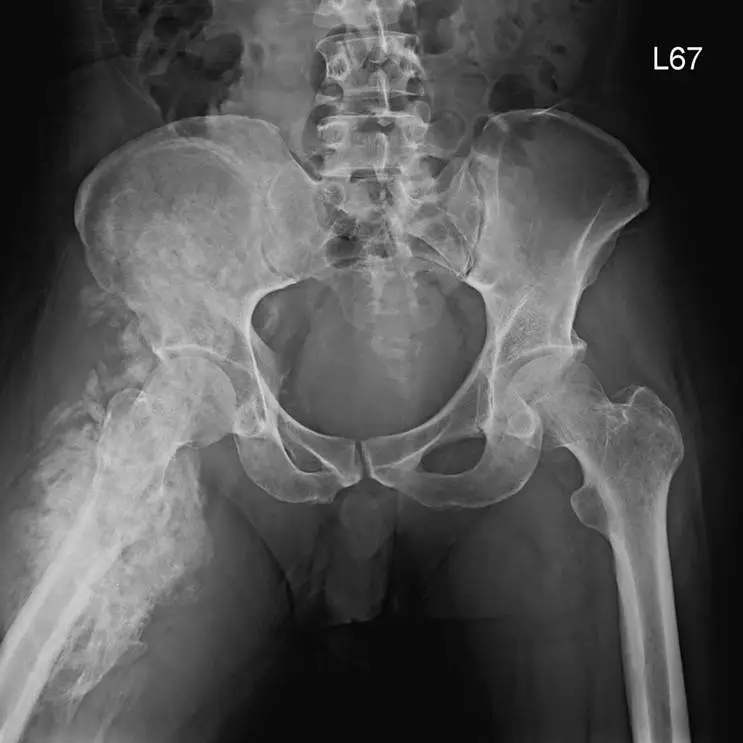

43歲男性病人, 6個月前中風合併右半側癱瘓, 4 個月前右側髖部開始腫脹,杜卜勒檢查無深層靜脈栓塞,最近的骨盆 X光片如圖,最可能的診斷為何?

中樞神經系統受損(如中風、脊髓損傷、顱腦外傷)後,患者常於傷後2週至12個月內在關節周圍軟組織內出現異位性骨化(heterotopic ossification, HO)。多見於髖關節,3~4個月為高風險期;早期X光難以顯影,通常3~8週可見鬆散「fluffy」或「popcorn」狀骨質,成熟期可演進為骨刺形成及髖臼與大腿骨橋接性骨化(Brooker 分級III~IV)(now.aapmr.org)。

正位骨盆X光片顯示:

- 右側近端股骨及對側髂骨周圍軟組織內,大片毛絨狀、鬆散透亮度偏高的新生骨化影(非原有骨骼輪廓);

- 骨化區域與骨幹分離,呈現骨刺樣投射,部分區域已有骨橋連通;

- 關節面無顯著侵蝕性破壞、無典型腫瘤破壞性裂隙,亦無環弧狀(ring-and-arc)鈣化或Codman三角;

- 無明顯經典Phemister 三合徵(周邊骨質疏鬆、邊緣侵蝕、關節腔持續狹窄),骨化主分布於軟組織。

以上影像最符合HO在中風後hemiplegia患者髖關節周圍的異位骨化特徵,成熟期可見廣泛軟組織骨化並可能導致關節僵直。